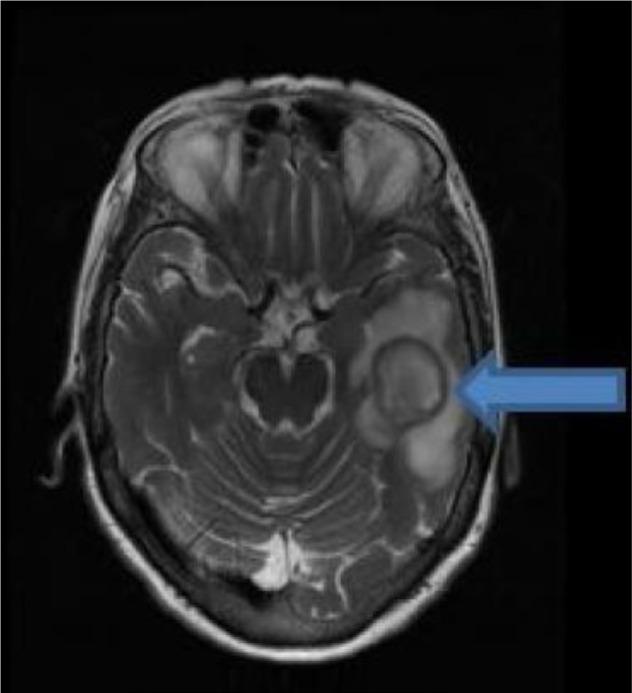

We present the case study of an elderly female patient who presented with expressive aphasia caused by brain abscess, secondary to infection. The 72-year-old female with a medical history of hypertension came to hospital for evaluation with word-finding difficulty, an expressive aphasia that began a few days prior to presentation. Computed tomography of the head showed a left temporal lobe mass-like lesion, with surrounding vasogenic edema. The patient was empirically started on courses of antibiotics. The next day, she was subjected to magnetic resonance imaging of the brain, which showed a left temporal lobe septated rim-enhancing mass lesion, with bright restricted diffusion and diffuse surrounding vasogenic edema consistent with abscess. The patient was also seen by the neurosurgery department and underwent stereotactic, left temporal craniotomy, with drainage, and resection of abscess. Tissue culture grew sensitive to ampicillin sulbactam. Subsequently her expressive aphasia improved.

我们报告了一例老年女性患者的病例研究,该患者因脑脓肿继发感染导致表达性失语。这位72岁的女性有高血压病史,因出现找词困难前来医院评估,这种表达性失语在就诊前几天开始出现。头部计算机断层扫描显示左侧颞叶有肿块样病变,周围有血管源性水肿。患者经验性地开始使用抗生素疗程。第二天,她接受了脑部磁共振成像检查,结果显示左侧颞叶有分隔的边缘强化肿块病变,弥散受限呈高信号,周围有弥漫性血管源性水肿,符合脓肿表现。神经外科也对该患者进行了会诊,并对其进行了立体定向左侧颞叶开颅手术,进行引流和脓肿切除。组织培养显示对氨苄西林舒巴坦敏感。随后她的表达性失语有所改善。